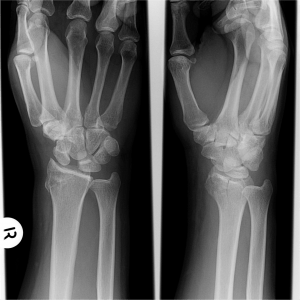

La pérdida de relación entre el escafoides y el semilunar, debida a la rotura de los ligamentos escafolunares, produce un tipo de inestabilidad parecido al de las pseudoartrosis de escafoides, excepto que en este caso es todo el escafoides el que sufre una anormal flexión palmar con subluxación dorsal de su polo proximal. El semilunar, no siendo ya controlado lateralmente por el escafoides, sigue al piramidal hacia una anormal extensión (DISI), a la vez que experimenta un característico desplazamiento en forma de supinación y traslación cubital. Dicho desplazamiento provoca una diástasis, de más de 3 mm del espacio escafolunar (Signo de Terry Thomas), con la consiguiente incongruencia articular radiocarpiana y mediocarpiana.

Los estudios incluyen una vista lateral estricta y vista anteroposterior con la muñeca en posición neutra, desviación radial y cubital. Además deben tomarse radiografías de la muñeca contralateral (comparación entre ambas). Se realiza medición en vista lateral, del ángulo escafolunar (trazar líneas a lo largo de los ejes del escafoides y semilunar). Se considera normal entre los 30º y 60º.